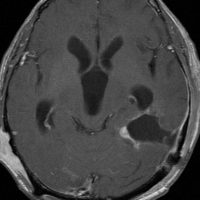

神経線維腫症1型に合併した退形成を示す anaplastic PXA

もともと停止性水頭症があり経過観察を受けていたNF-1の患者さんに発生したものです。嘔気と左片麻痺で発症しました。 開頭手術で亜全摘出(ほぼ全摘)しました。

術後に小さな腫瘍が残っていた(左の画像)ので54Gy/27frの放射線治療をしましたが,無効でした。結局,再開頭手術で残存腫瘍を摘出しました。3年後に同じ部位で再発(中央の画像)したので,また開頭手術で摘出しました。そのまた3年後に同じ部位で再発しました(右側の画像)。この様に,摘出しきれなければ治らないし,摘出できれば治る可能性の高い腫瘍です。腫瘍床での再発は多いものの,転移とか脳深部への浸潤性増殖は少ないといえる腫瘍です。放射線治療が効きにくいということを併せて,atypical meningioma WHO grade 2と似た性格を有しています。